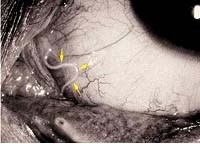

Từ 2005-2006, tổng số 4 bệnh nhân nhiễm Thelazia, vào khoa Cấp cứu của bệnh viện Croce và Carle ở Cuneo, Italy. 4 bệnh nhân nữ, tuổi từ 37-65, sống tại phía tây bắc Ý (43[độ]bắc và 6[độ]đông) và phía tây nam của Pháp (46[độ]bắc, 9[độ]đông), nơi mà nhiễm trùng trên chó, mèo, cáo nhiều. Tất cả bênh nhân có triệu chứng giống nhau (tiết nước mắt, viêm kết mạc, cảm giác có vật lạ trong mắt) vài ngày trước khi nhập viện. Tất cả bênh nhân đều dùng thuốc vì trước đó có cảm thấy sợi chỉ lơ lửng trong mắt. Bệnh sử chỉ ghi nhận trong số 3 bệnh nhân, bệnh nhân còn lại là một đàn ông không nhà đi đến y tế địa phương ở Nice, Pháp vì rối loạn tâm thần nặng, vệ sinh kém và tiểu đường. Không có bệnh nhân nào có bệnh về mắt hoặc di du lịch ra ngoài khỏi nơi ở, ngoại trùe bệnh nhân số 1 có đi làm gỗ ở Yenda (vùng Piedmont, Ý) khoảng 3 tuần trước khi có xuất hiện triệu chứng. Khám mắt cho thấy có giun nhỏ, mảnh nằm trong vòm kết mạc, giun được lấy ra bằng forceps sau khi gây tê tại chỗ bằng novocaine1%. Giun được bảo quản trong dung dịch ethanol 70% cho đến khi định loại hình thái học. Sau khi ký sinh trùng được loại bỏ khỏi mắt, dùng thuốc chống nhiễm khuẩn nhỏ mắt trong 7 ngày. Triệu chứng ở mắt biến mất trong vòng 2-3 ngày. Loài giun là T. callipaeda có khoang miệng, miệng mở ra với 6 vòng cạp và 6 vòng nổi (festoons). Các con giun cái trưởng thành đặc điểm có vị trí âm hộ nằm phía trước của điểm nối ruột thực quản, ngược lại con đực có 5 đôi nhú sau lỗ thải. Để xác định hình thể học, tiêu bản của 2 bệnh nhân 2 và 4 được phân tích. Phân tích bộ gen DNA từ mỗi con giun, phần giải trình tự của cytochrome c oxidase subunit 1 (cox1, 689 bp) bộ gen ty thể được khuyếch đại bằng kỹ thuật PCR. Amplicons đươc tinh khiết, sử dụng cột Ultrafree-DA columns (Amicon; Millipore, Bedford, MA, USA) và giải trình tự bằng cách sử dụng hệ thông ABI-PRISM 377 và Taq DyeDeoxyTerminator Cycle Sequencing Kit (Applied Biosystems, Foster City, CA, USA). Giải trình tự được xác định ở cả hai hướng và thẳng hàng bằng sử dụngClustalX program. Sự sắp xếp thẳng hàng nhìn có khác biệt, so sánh với trình tự có sẵn trong cox1 gene của T. callipaeda (thuộc GenBank accession nos. AM042549-556).

Triệu chứng lâm sàng của 5 bệnh nhân được tóm tắt (3 nam và 2 nữ; tuổi từ 57 -83) được khám tại bệnh viện Muikaiti và Tuwanokyouzon từ 1989-1999. Bệnh nhân số 1, 2, 3, 4 là bệnh nhân ngoại trú, nhưng bênh nhân số 5 là nội trú, nhập viện hơn 1 năm nay. Tất cả bệnh nhân nhiễm chỉ một bên một mắt (3 trường hợp nhiễm ở mắt phải và và 2 ca còn lại là mắt trái). Triệu chứng chính của bệnh nhân là cảm giác có vật lạ gì trong mắt, rối loạn thị lực và đau mắt (foreign body sensation, visual disorder, and ocular pain). Bệnh nhân thứ 5 có dấu hiệu sa sút trí tuệ, giảm trí nhớ (senile dementia). Khám lâm sàng cho biết sung huyết kết mạc, nang nhầy, có mặt con giun màu trắng trong kết mạc. Bệnh nhân không mô tả có ruồi trong mắt, nhưng cũng không giữ các súc vật như chó mèo, bò. Họ chưa bao giờ đến vùng Kyushu của Nhật Bản. Giun được loại bỏ (số lượng giun trong mắt bệnh nhân từ 2-5 con/ bệnh nhân) bằng forceps sau khi gây tê tại chỗ hoặc gây tê cục bộ và dùng kháng sinh nhỏ mắt. triệu chứng của các bệnh nhân được giải quyết nhanh chóng và không có tái phát. Sự có mặt của giun Thelazia callipaeda là một chẩn đoán xác định sau khi định loại.